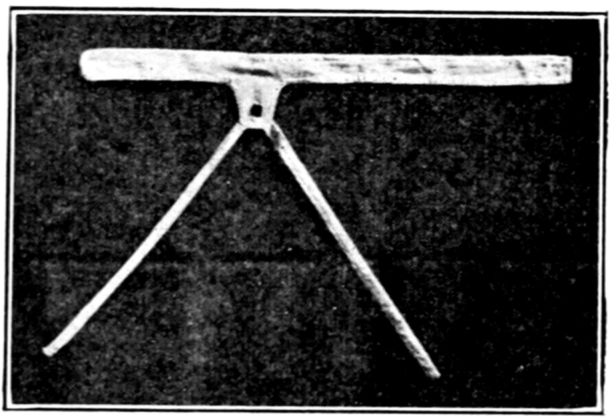

| xxiv184. | Band to hold baby’s legs while obtaining specimens of urine | 527 |

| 185. | Belt used to hold tube for specimen | 528 |